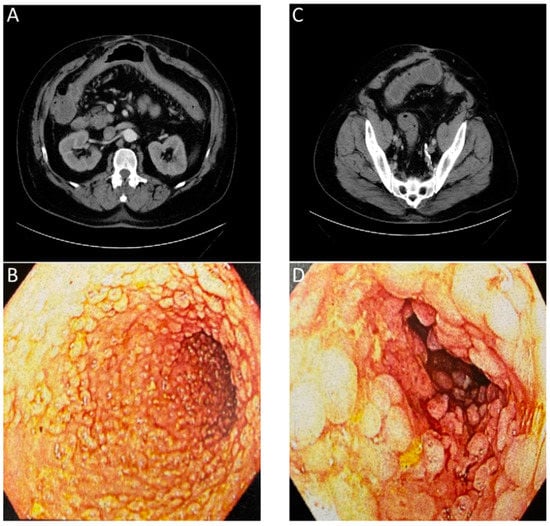

- Frickenstein, A.N.; Jones, M.A.; Behkam, B.; McNally, L.R. Imaging Inflammation and Infection in the Gastrointestinal Tract. Int. J. Mol. Sci. 2019, 21, 243. [Google Scholar] [CrossRef]

- Kilcoyne, A.; Kaplan, J.L.; Gee, M.S. Inflammatory Bowel Disease Imaging: Current Practice and Future Directions. World J. Gastroenterol. 2016, 22, 917–932. [Google Scholar] [CrossRef] [PubMed]

- Perlman, S.B.; Hall, B.S.; Reichelderfer, M. PET/CT Imaging of Inflammatory Bowel Disease. Semin. Nucl. Med. 2013, 43, 420–426. [Google Scholar] [CrossRef]

- Rath, T.; Bojarski, C.; Neurath, M.F.; Atreya, R. Molecular Imaging of Mucosal α4β7 Integrin Expression with the Fluorescent Anti-Adhesion Antibody Vedolizumab in Crohn’s Disease. Gastrointest. Endosc. 2017, 86, 406–408. [Google Scholar] [CrossRef] [PubMed]

- Turker, N.S.; Heidari, P.; Kucherlapati, R.; Kucherlapati, M.; Mahmood, U. An EGFR Targeted PET Imaging Probe for the Detection of Colonic Adenocarcinomas in the Setting of Colitis. Theranostics 2014, 4, 893–903. [Google Scholar] [CrossRef] [PubMed]